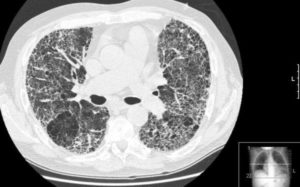

- Компьютерная и магнитно-резонансная томографияя;

К диагностическим методам, помогающим определить пневмофиброз. Относятся:

- МРТ;

- КТ.